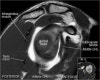

어깨 관절의 MRI 단면영상

- Axial section

1) Anterior & posterior labrum

2) Subscapularis muscle & tendon

3) Biceps long head tendon

4) GH joint cartilage

5) Osseous structure

6) 관절액 있을때 FSE T2 FS에서 Labrum 선명, 관절액 없을때 FSE PD FS에서 Labrum 선명